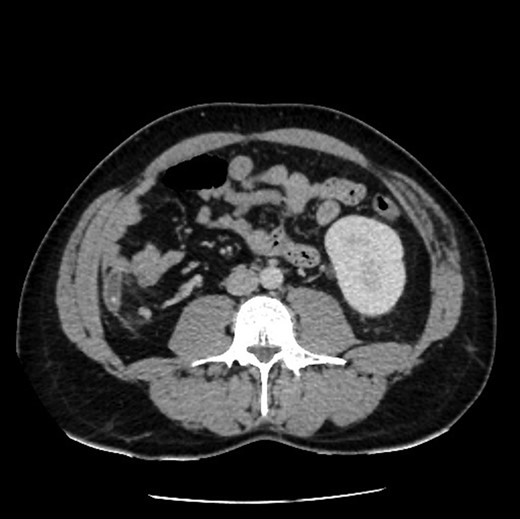

Upon review and clinically examination, the possibility of atypical appendicitis was raised due to the clinical history. Patient did not have any history of biliary colic or any epigastric pain. He was further investigated with CT abdomen which revealed the diagnosis of acute appendicitis in the right upper quadrant (Fig. 1). The atypical position of his presentation was a result of congenital right renal agenesis (Fig. 2). The appendix was lying on the right upper quadrant due to the absence of right kidney. He also had left kidney hydronephrosis and hypertrophy.

Axial view showing absence of right kidney due to congenital agenesis. Appendicitis with faecolith.